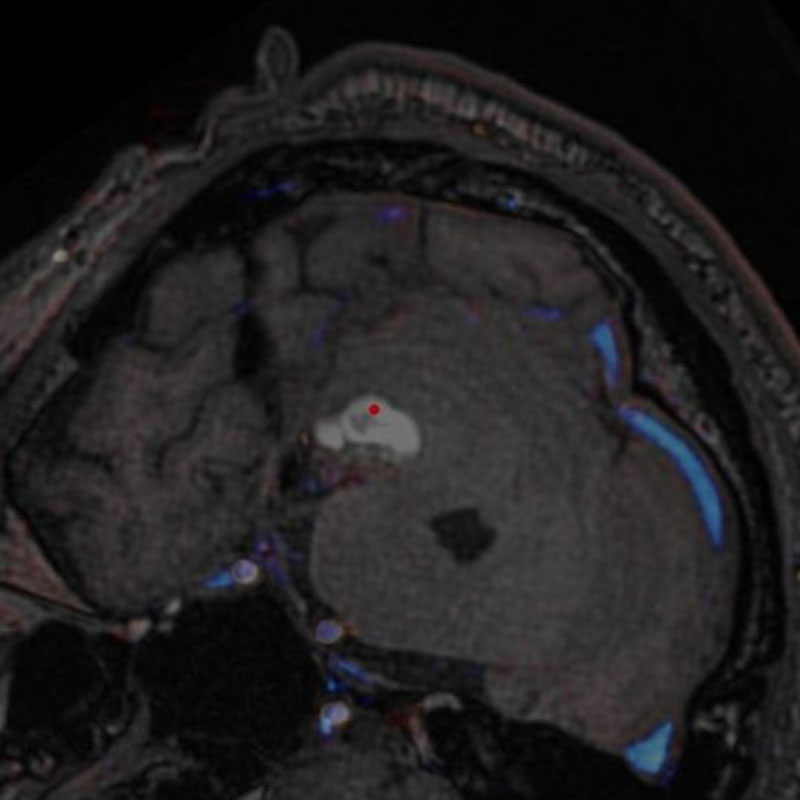

脳血管撮影

手術前